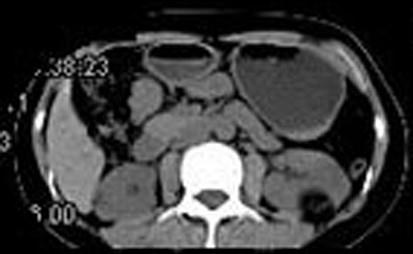

问题 女,38岁,体检时B超在左肾探及一中强回声光团,边界清,内部回声均匀,CT检查如图所示,下列说法正确的是 ( )

选项 A、考虑为左肾血管平滑肌脂肪瘤 B、考虑为左肾脂肪瘤 C、病灶与周围肾组织界限清楚 D、病灶密度为脂肪密度 E、左肾中部靠后方可见一类圆形低密度病灶

答案 BCDE